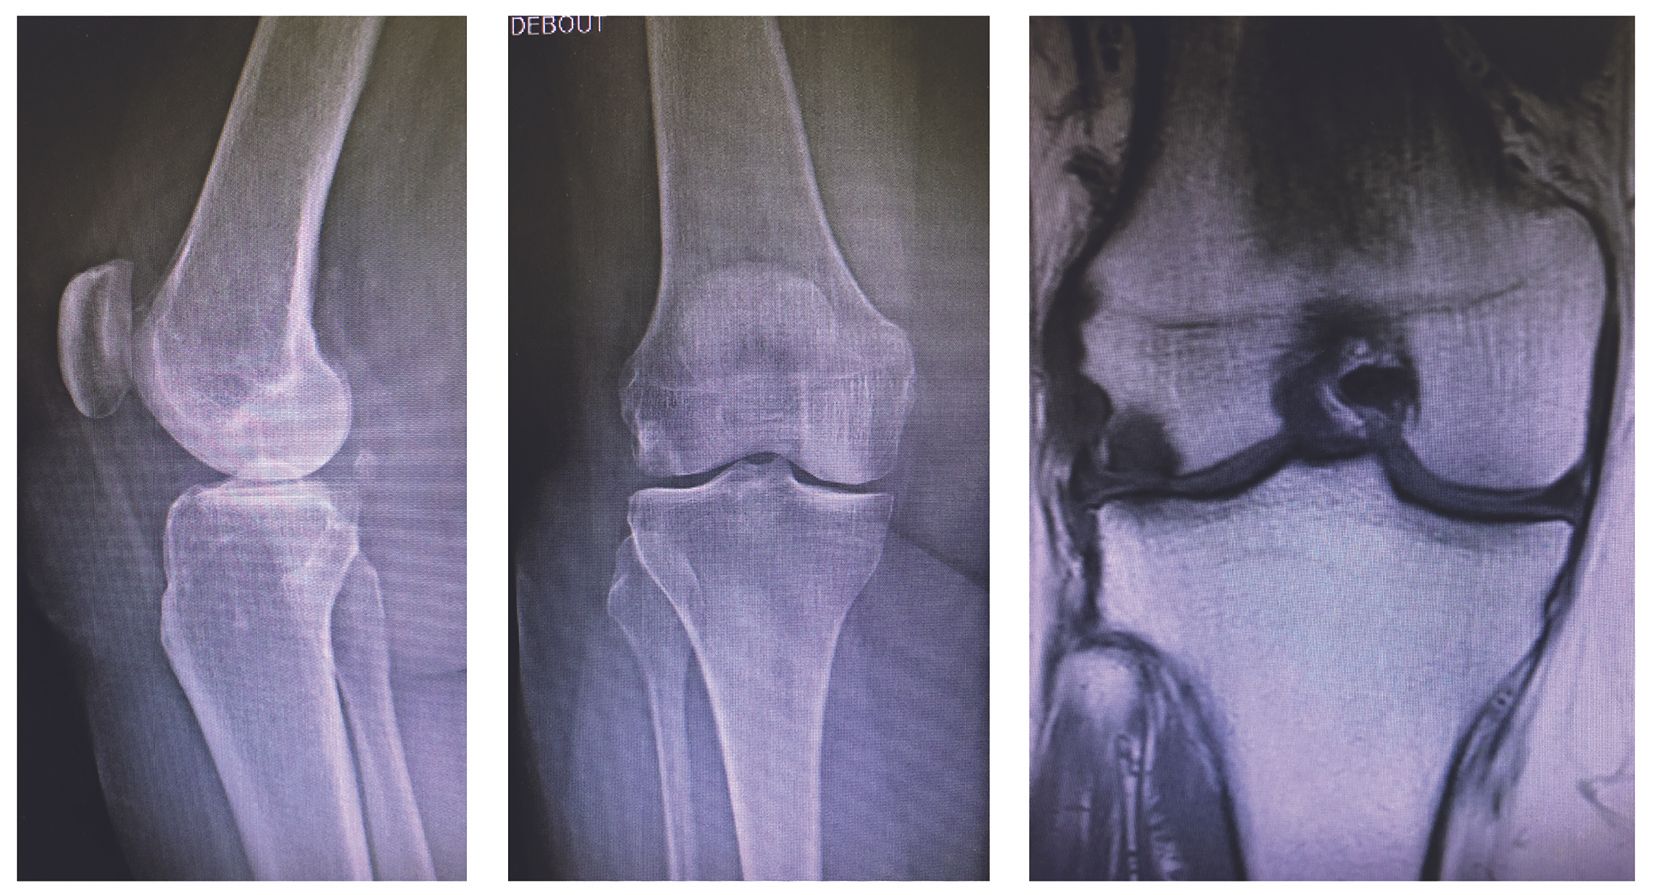

Isolated damage to the lateral tibiofemoral compartment is a determining factor for the indication. In some cases, the special 45° inclined PA view (Rosenberg or Lyon Schuss) will be necessary to identify the OA damage of the posterior femur condyle (Fig. 1). Local osteo-cartilage damage caused by spontaneous osteonecrosis (SPONK) of the lateral condyle is also a good indication (Fig. 2).

The preoperative deformity should be only moderate, preferably intra articular or epiphyseal, and reducible on stress x-rays. If the deformity is more severe (valgus > 15°) or outside the knee (extra articular) or especially if irreducible, the decision to perform an isolated UKA should be reconsidered because it could result in rapid wear and tear and/or early loosening. In these circumstances the advice is usually to perform a primary total knee replacement, or exceptionally to combine the procedure with an osteotomy to correct the extraarticular deformity.

Careful assessment is required to ensure the ligaments are intact (both cruciate, medial and lateral ligaments). This allows to perform UKA without touching the ligament envelope and any ligament balancing in the frontal plane should be avoided. The UKA should only fill the missing space which is the combination of the gaps created by the bony cuts and by the cartilage wear. The surgeon should leave a small ‘laxity safety margin’ of 1–2 mm to avoid overcorrection (Fig. 3).